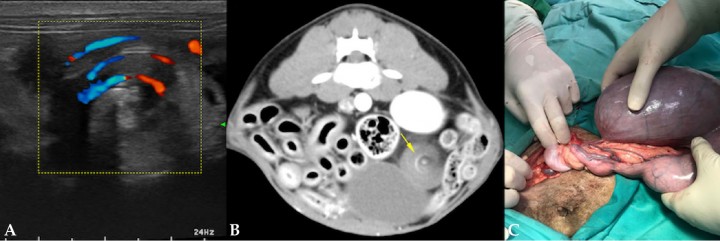

En este caso se realizó una ecografía abdominal en la que se observó el útero distendido con contenido hipoecoico con marcada celularidad (Fig. 3A). No se visualizaron fetos formados, aunque en el interior del útero se observaron estructuras hiperecogénicas que generaban sombra acústica, compatibles con restos óseos (Fig. 3B). Al seguir el recorrido del cuerno uterino izquierdo se apreció signo de remolino (whirlpool sign) que involucraba la vascularización uterina, indicativo de torsión (Vídeo 1). El Doppler color ayudó a la visualización de este patrón en espiral al resaltar el flujo sanguíneo de los vasos implicados, comprobándose posteriormente en la cirugía (Fig. 4).

<p>(<strong>A</strong>) Ecografía Doppler con signo de remolino indicativo de torsión. (<strong>B</strong>) Tomografia computerizada con signo de remolino. (<strong>C</strong>) Imagen intraquirúrgica que evidencia la torsión del cuerno uterino izquierdo.</p>

(A) Ecografía Doppler con signo de remolino indicativo de torsión. (B) Tomografia computerizada con signo de remolino. (C) Imagen intraquirúrgica que evidencia la torsión del cuerno uterino izquierdo.

Para una valoración completa del abdomen y descartar posibles complicaciones no visibles en la ecografía, se recomendó la realización de una tomografía computerizada (TC) abdominal prequirúrgica en la que se observó el útero muy distendido con contenido líquido y estructuras hiperatenuantes mineralizadas, apreciándose el mismo patrón en espiral o signo de remolino característico de torsión visto en ecografía, que afectaba al cuerno uterino izquierdo (Fig. 5) (Vídeo 2), sin otros hallazgos significativos.

En nuestro caso se realizó la ovariohisterectomía tras comprobar la presencia de torsión unilateral izquierda. Se determinó un grado de torsión de aproximadamente 1440º (4 vueltas completas de 360º). Sorprende en este caso que, a pesar de presentar un grado de torsión muy grave, la sintomatología de la paciente no se correspondía con la de un abdomen agudo, lo que nos hace pensar que la torsión era reciente. La cirugía se llevó a cabo sin complicaciones y la evolución fue muy favorable. Con respecto a las estructuras de opacidad hueso observadas en las radiografías, y cuya localización intrauterina fue diagnosticada mediante ecografía y TC, se confirmó que se trataba de restos fetales momificados. Como la muerte del feto ocurrió una vez iniciada la mineralización de su esqueleto, una completa reabsorción fetal no fue posible y en su lugar se produjo la momificación.

El signo de remolino visto en ecografía y TC fue el factor clave para alcanzar el diagnóstico. Este patrón en espiral indicativo de torsión no siempre es visible y debemos tener en cuenta que la ausencia de este signo no descarta la presencia de una torsión.